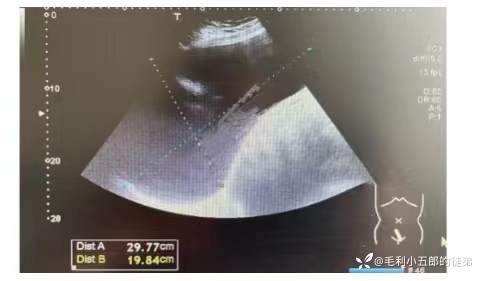

1.妇科超声(2023-5-30我院): 阴腹联合扫查:子宫后位,大小形态如常,内膜厚约: 0.7cm.肌层回声均质。左侧卵巢大小: 4.4x2.7cm。左侧附件区探及一无回声,大小约3.9x3.1cm,壁薄透声佳,其内未探及明显血流信号。盆腔探及一无回声,大小约29.8x23.1x19.8cm,透声佳,未见明显血流信号。左侧附件区囊肿,盆腔无回声,源于卵巢?